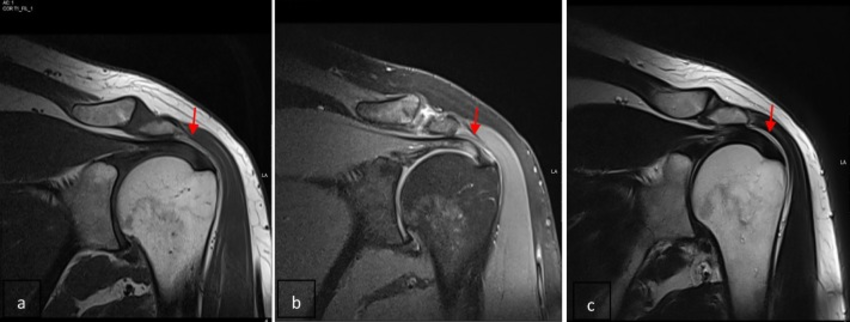

Here are some MRI images:

MRI images provide multiple "views" of the anatomy; these are usually the "T1-weighted", "T2-weighted", and "PD-weighted" views, which we'll discuss more in later lectures.

The combination of views, of course, provides more information that a single view. A tissue classification at a pixel can often be made by looking at the three different values of the corresponding pixel in the three views.